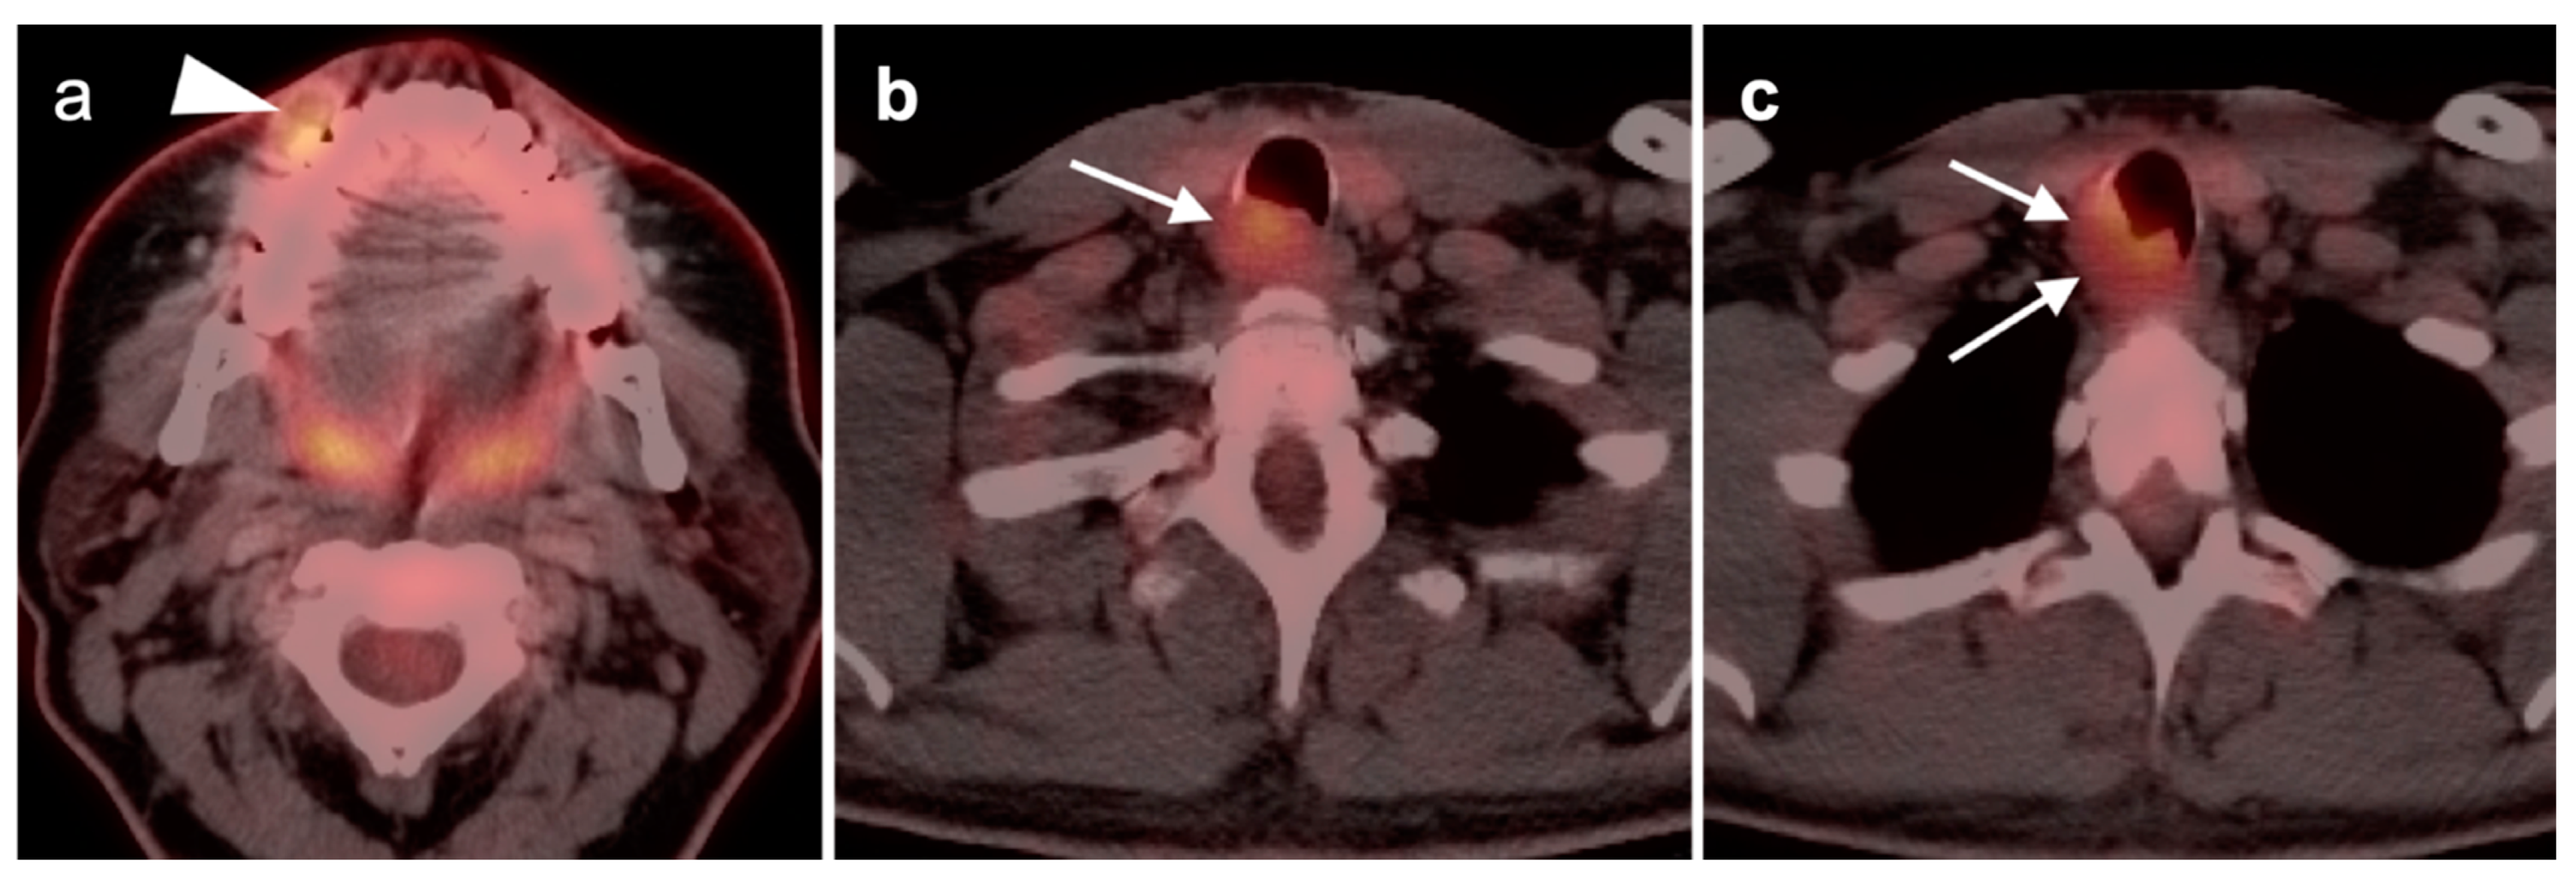

2.2. Squamous Cell Carcinoma of the Head and Neck (SCCHN)

- Oral cavity squamous cell carcinoma

- 2.

- Oropharyngeal squamous cell carcinoma

- 3.

- Hypopharyngeal squamous cell carcinoma